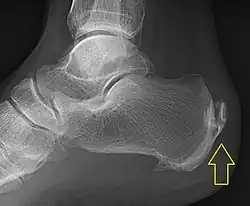

Calcification deposits forming an enthesophyte within the Achilles tendon at its calcaneal insertion. The Achilles tendon is wider than normal, further suggesting inflammation.

Achilles tendinitis is usually diagnosed from a medical history, and physical examination of the tendon. Projectional radiography shows calcification deposits within the tendon at its calcaneal insertion in approximately 60 percent of cases.[16] Magnetic resonance imaging (MRI) can determine the extent of tendon degeneration, and may show differential diagnoses such as bursitis.[16]